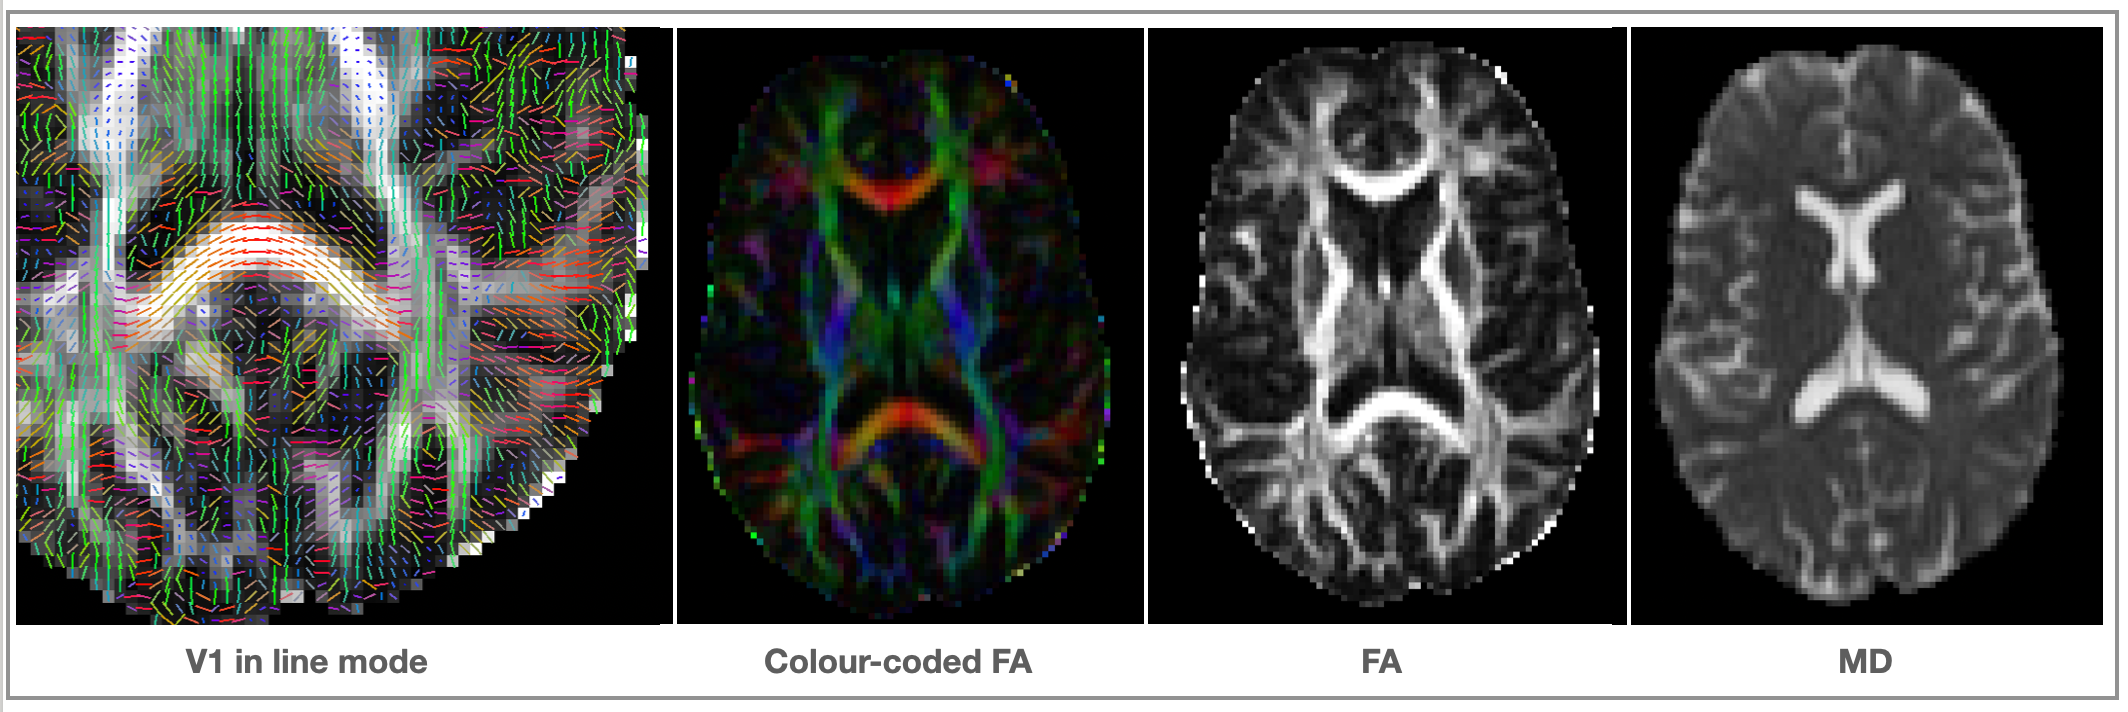

Outputs of dtifit

<basename>_V1- 1st eigenvector<basename>_V2- 2nd eigenvector<basename>_V3- 3rd eigenvector<basename>_L1- 1st eigenvalue<basename>_L2- 2nd eigenvalue<basename>_L3- 3rd eigenvalue<basename>_MD- mean diffusivity<basename>_FA- fractional anisotropy (isotropic ~ 0; stick-like ~1)<basename>_MO- mode of the anisotropy (oblate ~ -1; isotropic ~ 0; prolate ~ 1)<basename>_S0- raw T2 signal with no diffusion weighting